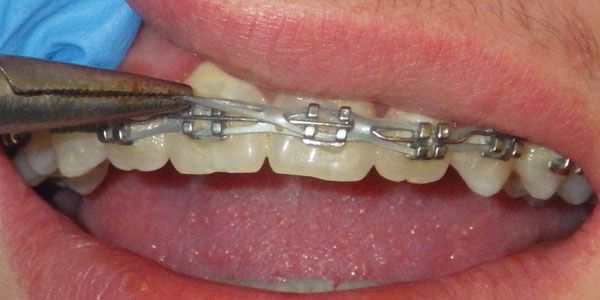

Dr. Jay B. Burton discusses the aspects of CBCT imaging that improve treatment planning and diagnostics CBCT has changed everything in my practice life — from treatment planning to treatment options to mechanotherapy, and even evaluation of treatment results. At this point, it is honestly difficult for me to imagine practicing without it. In discussions […]